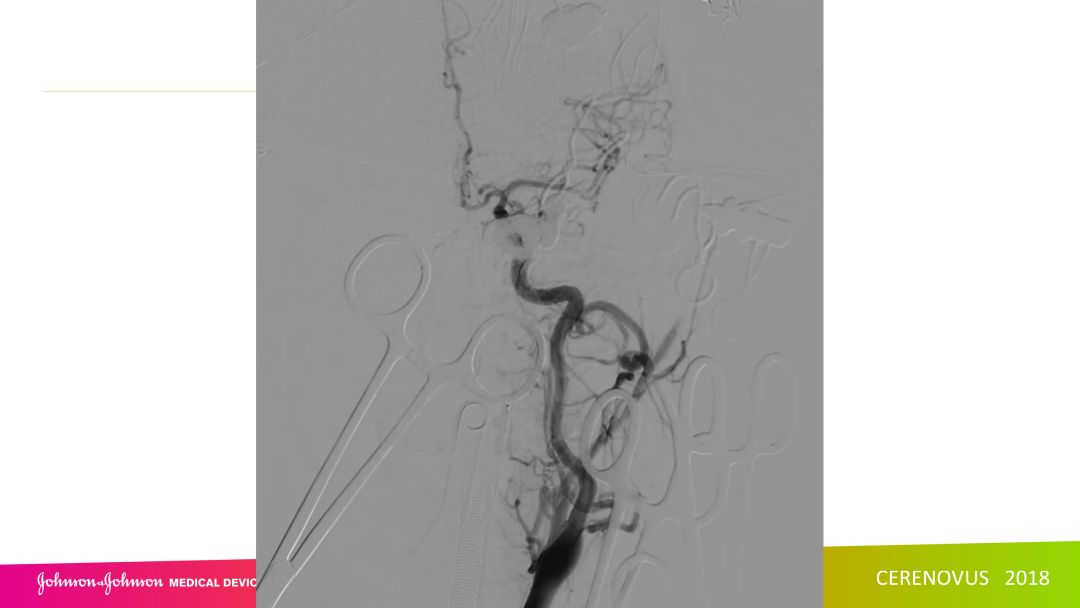

复合手术治疗海绵窦区硬脑膜动静脉瘘一例